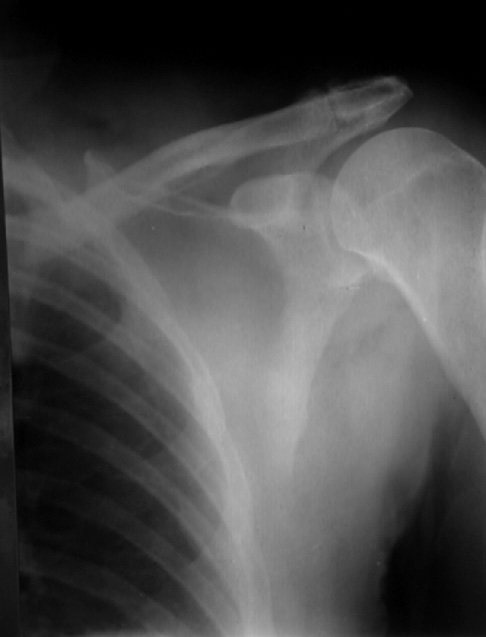

To provide an opportunity for the comparison of image scanning techniques, we are posting in the "Digital Images" forum of the HWB Home Page (http://www.hwbf.org/hwb/) an AP Shoulder film scanned with a $16,000 Howtek Scanmaster DX Xray scanner and a $200 "Snappy" video digitizer. The "Snappy" plugs into the video port of a camcorder or VCR. JPEG compression of either 5:1 or 10:1 are applied to the scans. We would be interested in any feedback with respect to the diagnostic quality of these images.

Click images to enlarge.ROW 1: JPEG 5:1 compression